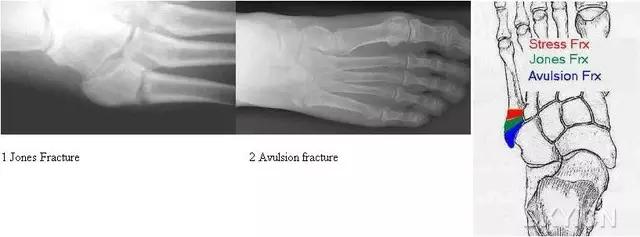

14.第五跖骨骨折

第五跖骨基底部骨折的不同类型:Stress 骨折;Jones 骨折:第五跖骨基底部以远 1 英寸内的骨折称为 Jones 骨折; Avulsion 骨折。

(来源:Radiopaedia)

Stress 骨折(来源:OrthoInfo-AAOS)

Jones 骨折正位片(来源:Radiopaedia)

Jones 骨折斜位片(来源:Radiopaedia)

第五跖骨骨折还有 dancer’s fracture。

dancer’s fracture 正位片(来源:footEducation)

dancer’s fracture 侧位片(来源:footEducation)